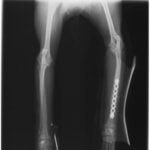

トイプードル 右遠位橈尺骨短斜骨折のALPSによる内固定

Locking Compression Plate

LCPは、スクリュー(ネジ)とプレート(金属の板)をロックする特殊な構造により骨折部位を固定する新しい世代のプレートシステムです。ひとつのホールでロッキングスクリューとスタンダードスクリューの使用を選択できるユニークな構造をしているため、骨折断端間の圧迫を目的とした従来型プレート固定法に加え、高い角度安定性を有するロッキングスクリューを用いた固定法の選択が可能です。従来のプレートシステムでは困難だった部分の骨折や癒合不全の症例に高い治療効果をもたらします。